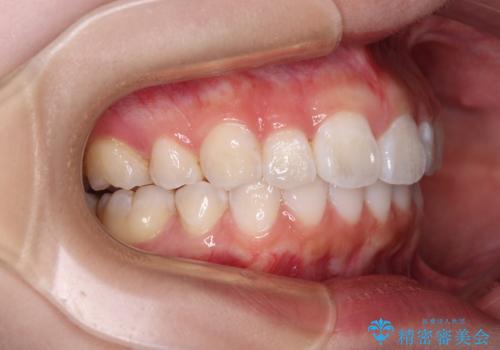

- 上下前歯の叢生を気にして来院された患者様です。

インビザラインでの治療を希望されていて、デコボコの程度が中等度であり、安価なパッケージにて対応可能と判断されたため、インビザライン・モデレートを用いて矯正治療を行うこととしました。

インビザライン・モデレートは、製作できるアライナーの枚数に制限があるため、移動可能な量に限りがあるものの、インビザライン・ライトよりも枚数が多いため、幅広い症例に対応可能です。